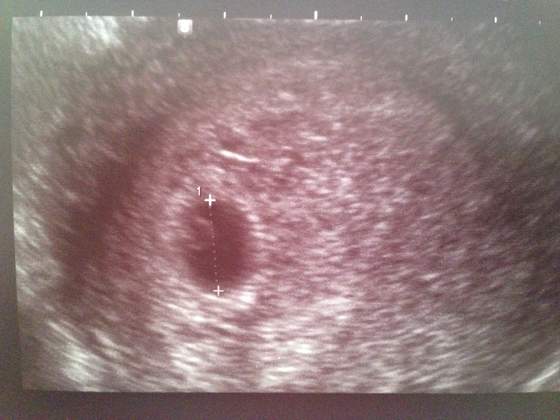

Mam jeszcze pierwsze zdjęcie usg, Twój zarodek (a właściwie dopiero jest to pęcherzyk ciążowy) pewnie wygląda tak samo. Czyli czarna plamka z jaśniejszą w środkuZobacz załącznik 689443

Mi pokazało, że wymiar jest w normie czyli 10.4mm